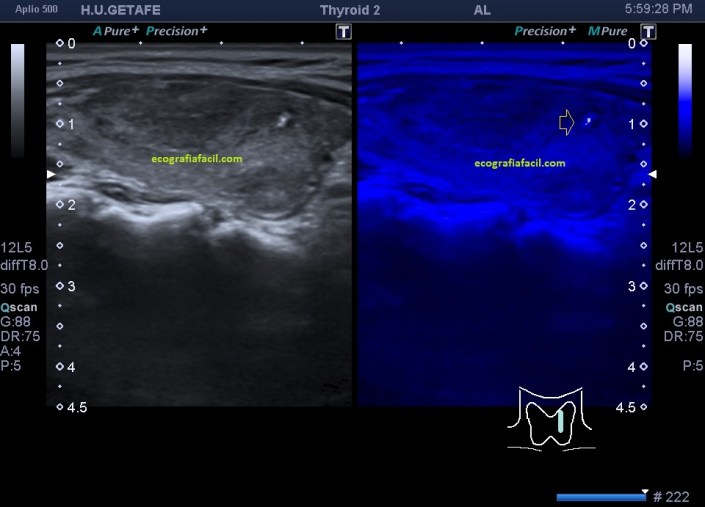

Ahora, en el caso que estas viendo hoy, con la información clínica de la que disponemos y lo que nos cuenta la paciente observamos las siguientes imágenes. Sumada a la imagen 3 te enseño un corte longitudinal de uno de los lóbulos tiroideos en la imagen 4. En la imagen 4 observas un lóbulo heterogéneo (diferentes tipos de grises) cuando deberíamos ver una glándula homogénea.

Cuando estudiamos concienzudamente la ecoarquitectura del Tiroides es momento de estudiar su apariencia vascular y descubro esto inmediatamente que me llama poderosamente la atención y que ves en la imagen 5, mira:

En la imagen 6 observas la misma imagen con el modo angio activado (doppler power), con el que vamos a conseguir observar la vascularización de flujo lento, por eso en el mismo corte puedes ver como si hubiera más vascularización que ves en la imagen 5.

En la imagen 7 tienes el corte del lado contralateral del tiroides, donde con el modo angio activado, puedes ver además que ese lóbulo tiene más actividad vascular que el izquierdo.

En conclusión, con esta vascularización (infierno tiroideo), el aspecto general de la glándula y la información clínica detallada del informe radiólogico, y por supuesto, pruebas analíticas (hipertiroidimo), otras pruebas imágenes y la historia clínica (taquicardias) detallada de la que disponía la endocrina al cargo de la paciente, se diagnosticó una Enfermedad de Graves-Basedow.